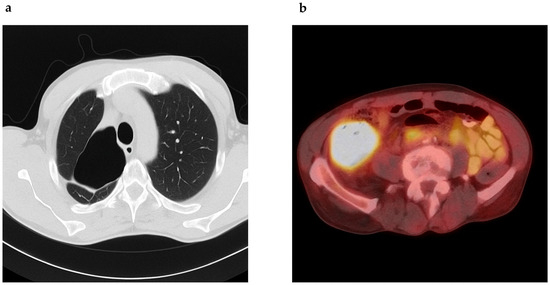

He was initiated on a regimen of clarithromycin, ethambutol, and rifampin. Despite some clinical improvement, sputum cultures remained persistently positive. In 2016, moxifloxacin was added to intensify therapy. By 2019, he experienced worsening symptoms, and drug susceptibility testing revealed resistance to clarithromycin, amikacin, ciprofloxacin, and linezolid, suggestive of treatment-emergent resistance, while retaining sensitivity to ethambutol, rifampin, and clofazimine (Table 1). He was treated with ethambutol, rifampin, azithromycin, and clofazimine (compassionate use), though clofazimine had to be discontinued due to insurance constraints. He declined inhaled aminoglycosides. Eventually, due to gastrointestinal intolerance and persistent symptoms, he self-discontinued therapy in early 2022. Chest CT in mid-2022 revealed progression, with cavitary lesions measuring up to 8.2 × 7.4 cm (Figure 1a). Sputum AFB remained positive, with drug susceptibility revealing resistance to clarithromycin and moxifloxacin, but susceptibility to bedaquiline, omadacycline, tedizolid, and inhaled liposomal amikacin. Simultaneously, workup for his chronic abdominal pain revealed a cecal mass. Colonoscopy confirmed a fungating mass in the cecum/ascending colon and biopsy of the mass confirmed a moderately differentiated adenocarcinoma with loss of MutL promoter homolog 1 (MLH1) and postmeiotic segregation gene 2 (PMS2), suggestive of mismatch repair deficiency (MMR-d) (Figure 2). Lynch syndrome was ruled out by genetic testing. A positron emission tomography (PET)-CT scan showed a hypermetabolic ascending colon mass and multiple fludeoxyglucose (FDG)-avid abdominal lymph nodes (Figure 1b). Lung cavities were also PET-avid. Hence, we performed a lung biopsy, which came back negative for malignancy. His baseline carcinoembryonic antigen (CEA) was at 138.2 ng/mL (normal < 4 ng/mL).

Figure 1. (a) Chest CT reveals a thick-walled cavitary lesion in the apex of the right lung measuring approximately 8.2 × 7.4 cm with other blebs noted in the right upper lobe. (b) PET scan reveals a 7.4 cm transaxial markedly hypermetabolic mass in the ascending colon with SUV max 26.0.